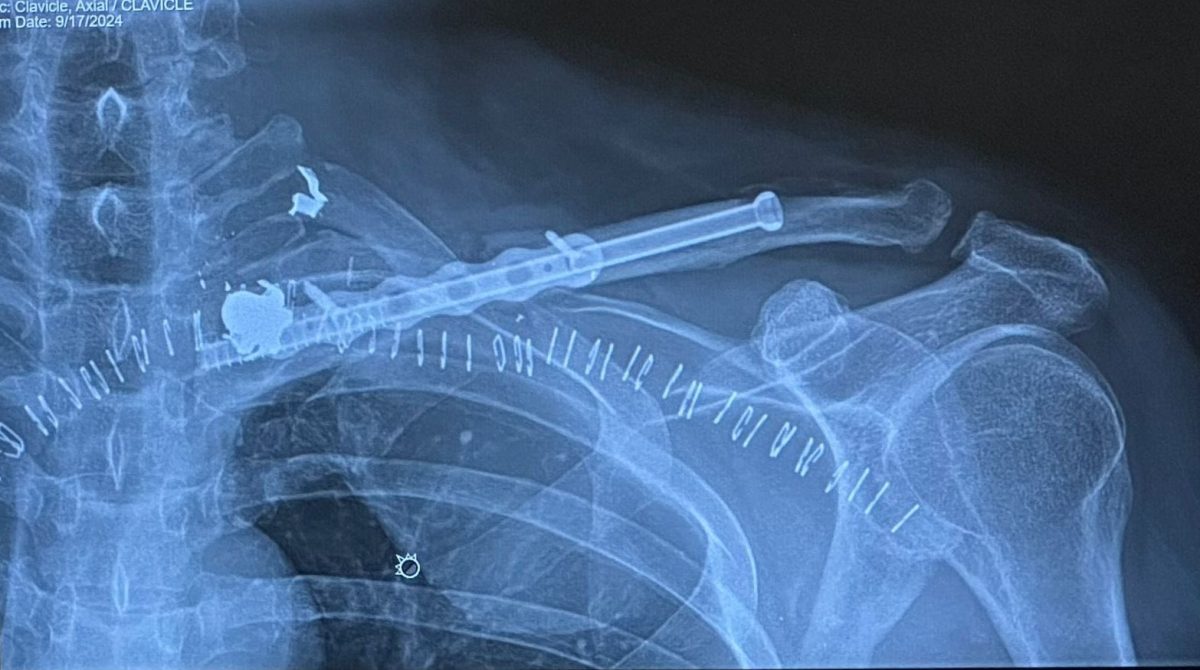

Milanés ya había compartido que le realizaron más de 30 transfusiones de sangre, pero ahora confirma que aún tiene cuatro fragmentos de bala en su cuerpo y un tubo de titanio en su clavícula izquierda, implementado para reemplazar la función de este hueso clave en la estabilidad del hombro.

El empresario, que también es activo en redes sociales, compartió imágenes que muestran un tornillo de al menos 10 centímetros en su clavícula. Este atraviesa su hombro izquierdo en dirección a la columna vertebral, revelando la magnitud de la intervención quirúrgica. Además, las imágenes evidencian unas 45 grapas metálicas que mantuvieron cerrada la herida, donde se extrajeron varios proyectiles.

Fuentes consultadas por la redacción de nuestro medio con conocimiento de tema, explicaron que el tornillo de titanio fue insertado para reemplazar de manera momentánea la función de la clavícula, un hueso crucial que mantiene el hombro elevado y estable, en conjunto con el omóplato y la articulación acromioclavicular. Esta estructura le permite mayor estabilidad en la articulación del hombro, algo esencial para su recuperación.